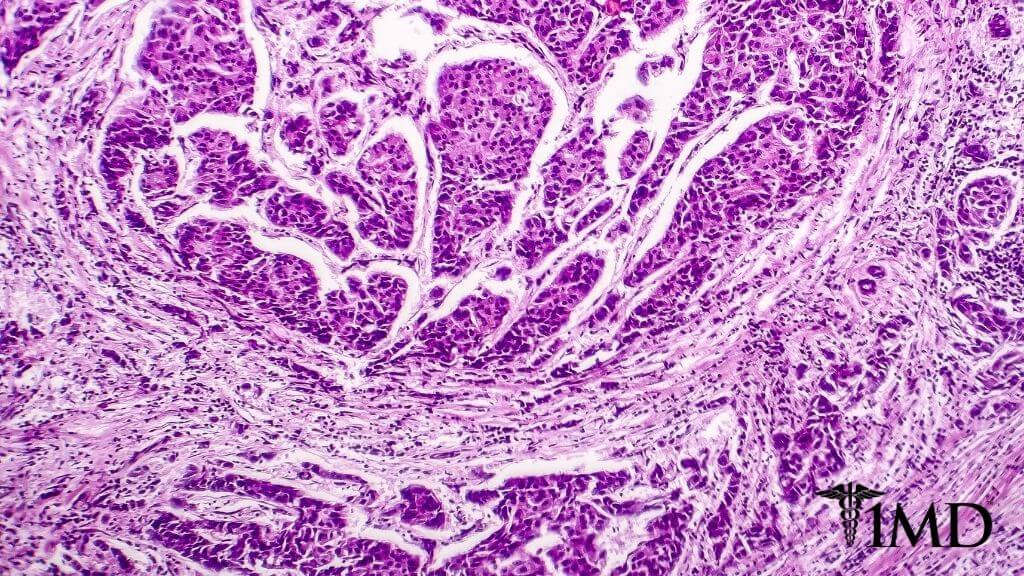

Cancer on the Move

The spread of cancer is complex, and with mortality rates increasing because of cancer metastasis, concern has grown in the cancer research community. Cancer cells seek environments where they can thrive, and a cyclical series of events drives cancer to grow and spread.

Stressed cells get damaged, which causes inflammation and genetic abnormalities to intensify. This allows cancer cells to develop because the inflammation, which can be reduced through supplements, breaks down cell signaling, allowing tumors to form and eventually spread.

The driving force behind cancer metastasis is inflammation because it increases tissue damage and encourages epigenetic changes. We originally thought that the genes we were born with could not be changed, but the discovery of cancer proved us wrong.

With the discovery of immune cells in tumor samples, scientists realized that inflammation plays a role in the development of cancer too. It’s why controlling inflammation is so important.

When a tumor starts to grow from a few cells that have wandered away from their home (likely via the interstitium), it scavenges oxygen from its surroundings. As it grows, it becomes more demanding and begins to develop genetic faults.

As they struggle to survive, they release chemicals that attract immune cells, which are rushed to the scene via an inflammatory response. Once inside the tumor, these immune cells release molecules that trigger the growth of blood vessels and bring in all the oxygen that the tumor needs to survive.